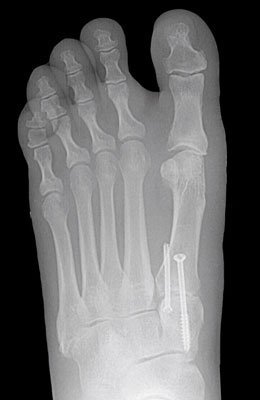

Before

After

Osteotomy Bunionectomy after

Osteotomy Bunionectomy

In this procedure (also known as an “Austin Bunionectomy), a cut in the bone was made, and the bone was shifted to realign the joint. A screw was placed to hold this new alignment in place. Notice the improved alignment of the great toe joint.